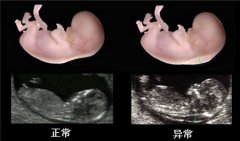

怀孕三个月左右,孕妈去医院产检,医生就会告诉该做NT了。 NT检查到底是查什么呢 ...[详情]